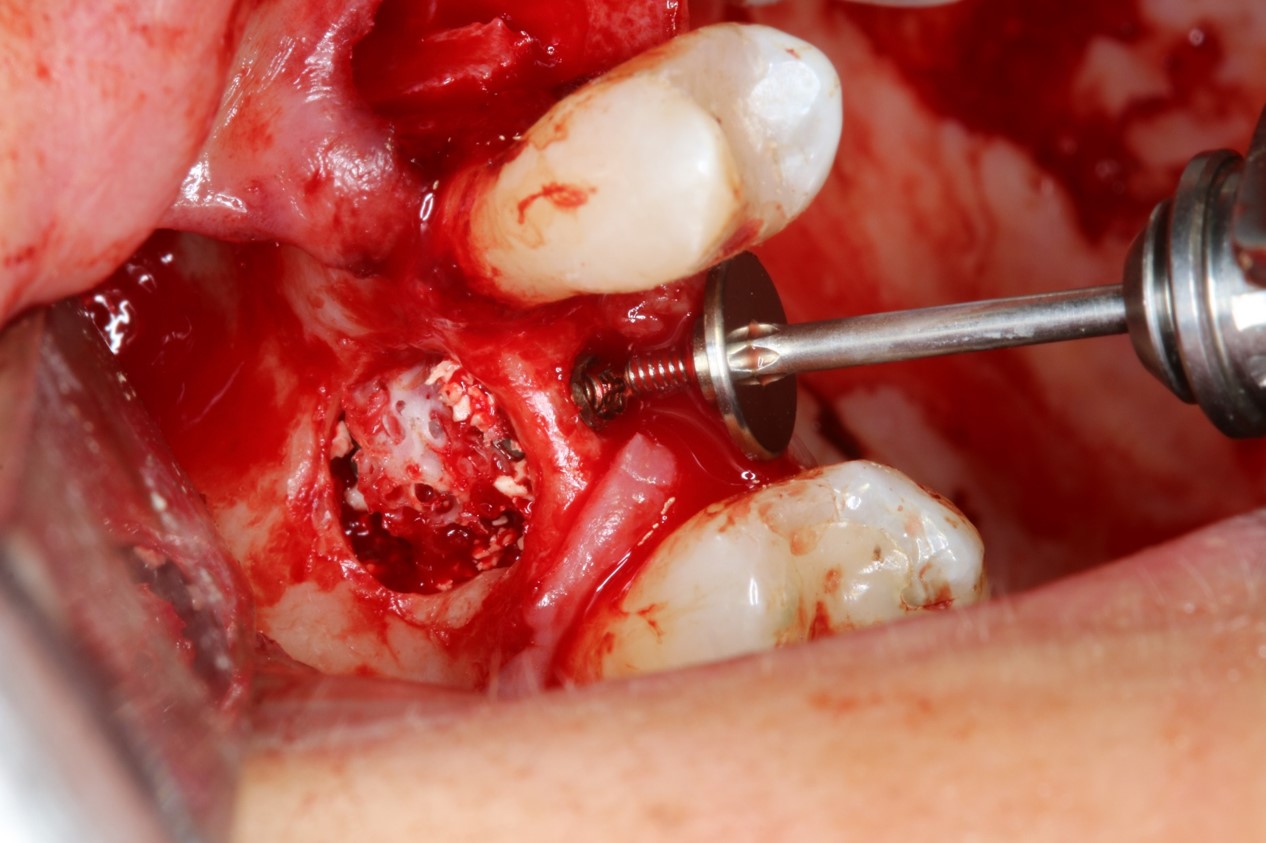

Vertical augmentation: Preparation of ring bed in atrophic mandibula (third quadrant)